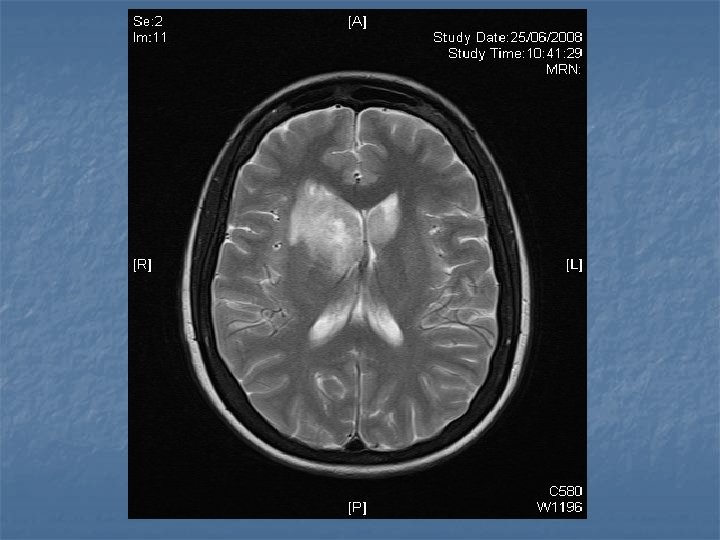

n n n PRETREATMENT INVESTIGATIONS: FBC, Renal and liver function, LDH, urate, Ig. GS. Histology review. Marrow aspirate+trephine (cytogenetics, immunology) CD 4 , HIV viral load. CT Scans. (MR Brain) (PET scan ) Echo / LVEF CMV, Hep B+C, Toxoplasma serology MAI screen. LP for CSF cytology +/- intrathecal Rx. (DLBC , Burkitt, Plasmablastic).

n n n PRIMARY CNS LYMPHOMA Typically occurs with marked immunosuppression CD 4<50. Marked reduction in incidence post HAART. Always EBV positive DLBC NHL. Commonly multifocal brain lesions. n High dose methotrexate iv Followed by brain XRT. n Poor prognosis survival months to 1 -2 years. n